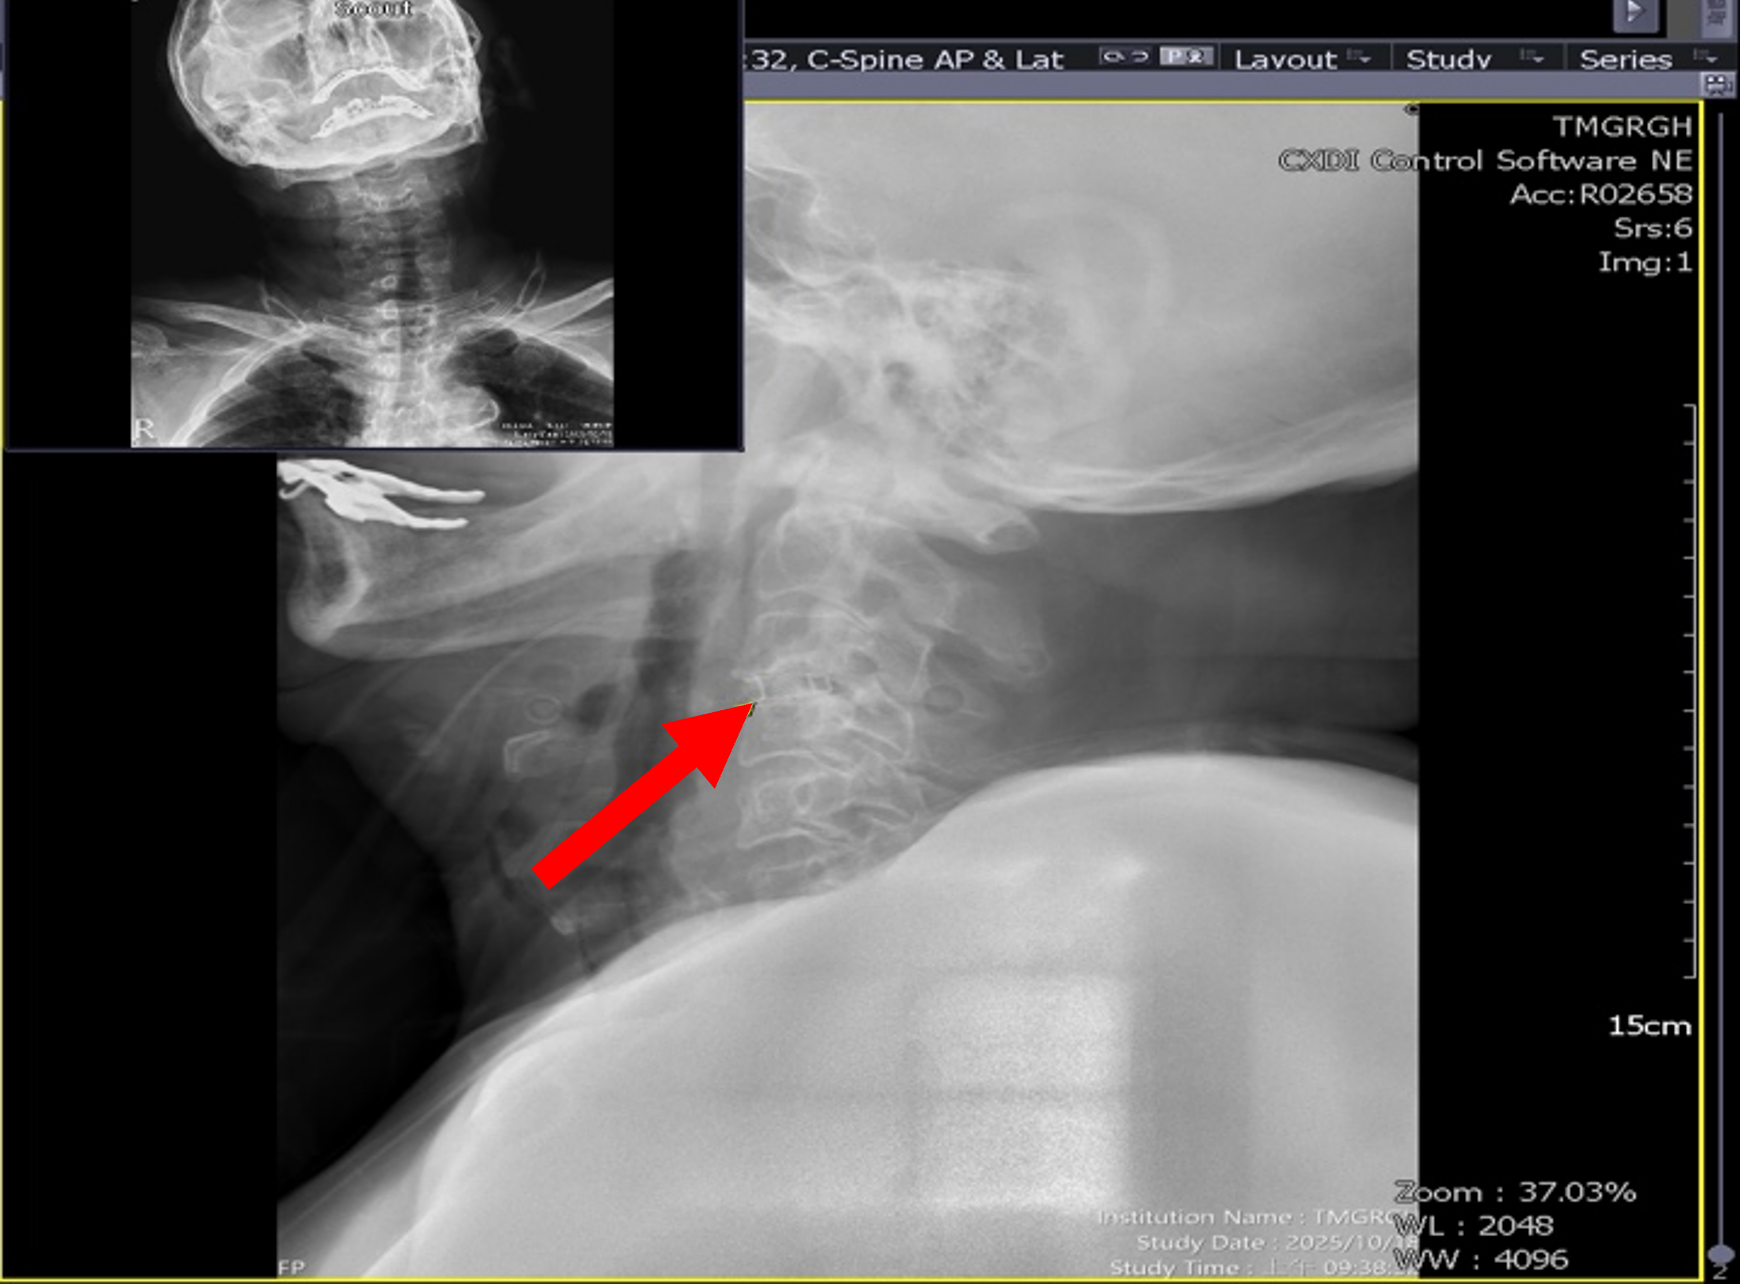

圖二、手術於頸椎第3至第4節植入支架融合。